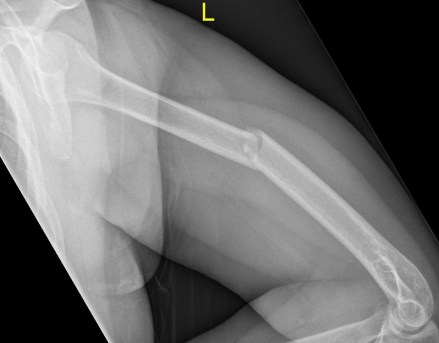

Question 4 |

A geriatric patient presents thus after gardening and hearing a popping sound. Given the best matched diagnosis, what is the root value of the affected muscle’s innervation?

Select all which may apply.

C5 Hint: C | |

C6 | |

C7 | |

C8 | |

T1 |

Study the image below and answer the following question:

Which clinical sign is mostly likely given the lesion seen?

Atrophy of coracobrachialis

| |

Atrophy of extensor carpi radialis longus

Atrophy of flexor digitorum profundus

Loss of biceps and triceps reflexes

Paraesthesia of the lateral forearm

|

- Knipe, H. (2020). Midshaft humerus fracture. Available: https://radiopaedia.org/cases/midshaft-humerus-fracture?lang=gb. Last accessed August 2020.